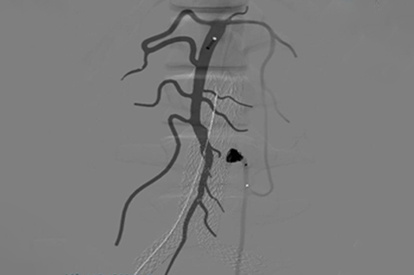

EVAR (Endovascular Aneurysm Repair) Module

Renal Intervention Module

Iliac Intervention Module

SFA Intervention Module

Lower Extremities CTO Module

Below The Knee Module